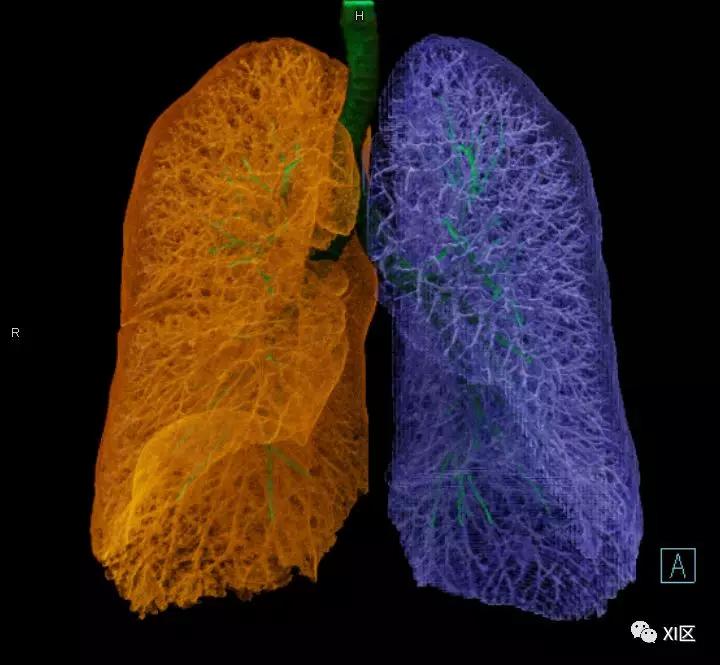

气管支气管树与两肺融合显示

气管树的解剖

人的支气管(第1级)至肺泡约有24级分支。支气管经肺门入肺,分为叶支气管(第2级),右肺3支,左肺2支。叶支气管分为段支气管(第3~4级),左肺8支、右肺10支。段支气管就是肺的分段的依据。段支气管反复分支为小支气管(第5~10级),继而再分支为细支气管(第11~13级),细支气管又分支为终末细支气管(第14~16级)。从叶支气管至终末细支气管为肺内的导气部。终末细支气管以下的分支为肺的呼吸部,包括呼吸细支气管(第17~19级)、肺泡管(第20~22级)、肺泡囊(第23级)和肺泡(第24级)。

气管支气管形如树状,因此也称气管支气管树。

气管树与左右肺的关系